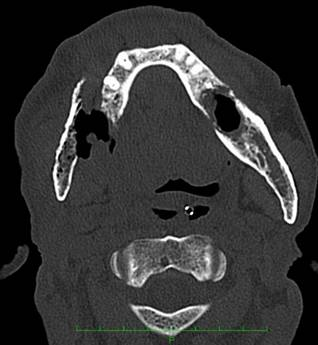

症状も他の顎骨壊死と類似し、痛みやしびれ・排膿など多様で、進行すると感染の増悪や病的骨折を併発します。炎症が広範囲に及び、開口障害(口が開かなくなること)が生じている。

開口障害が重篤な場合、口から食事を摂取することが困難となる。本来CTで白く映るはずの皮質骨が融解し、数か月後には病的骨折を発症した。

下顎下縁に及ぶ骨吸収像を認めた。

下顎骨の中に下歯槽神経が走行している。

骨融解が神経に及ぶと、激しい痛みを生じる。保存的な治療では除痛が困難と診断された場合は、手術が必要となることがある。

この患者さんは腐骨除去(下顎骨区域切除)と腓骨皮弁移植(足の骨と皮膚の移植)を施行した。現在は痛みなく生活されている。